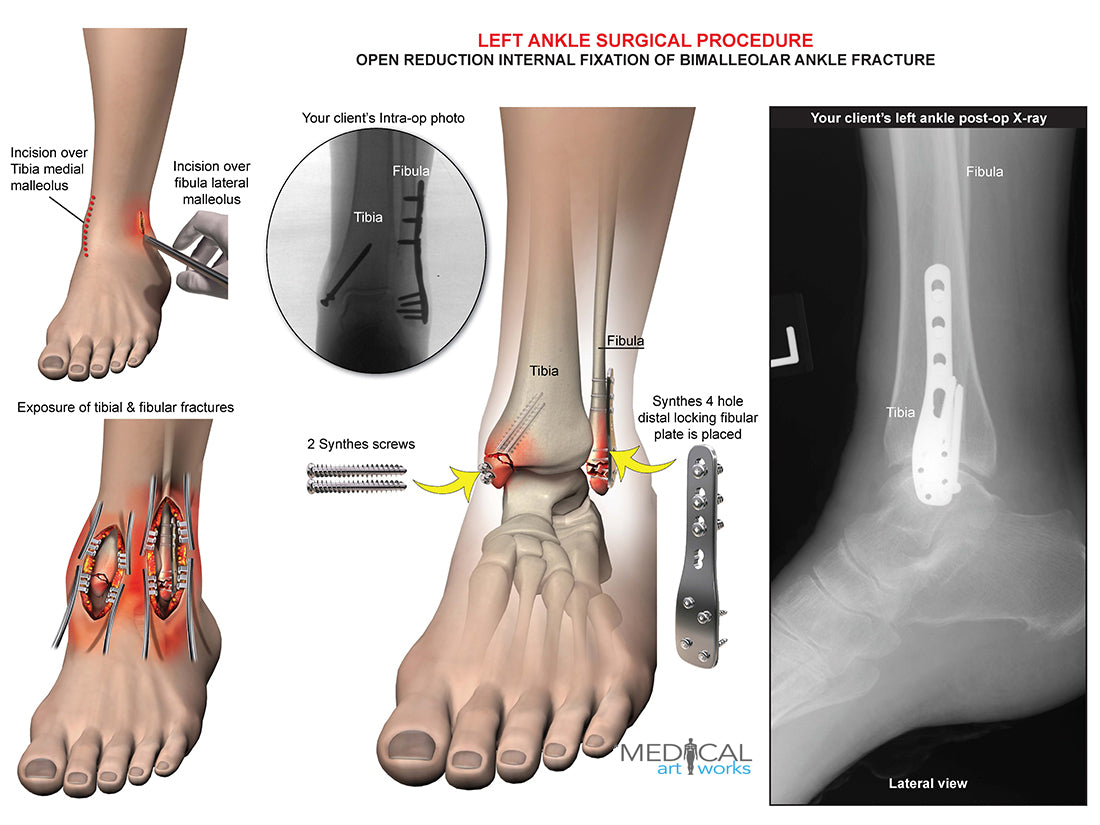

Left ankle and tibia bimalleolar fracture -ORIF

Left ankle and tibia bimalleolar fracture -ORIF

Open reduction internal fixation of bimalleolar ankle fracture. Synthes 4 hole distal locking fibular plate is placed, 2 Synthes screws. Add you own client's post-op x-ray.